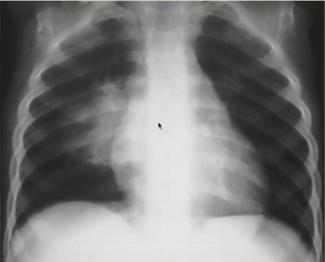

Example 1 主诉:30周早产儿出生后呼吸困难。

胸片特点:气管插管;弥漫白色“铅笔尖”样白色小点。

诊断:新生儿呼吸窘迫综合症(表面活性物质缺乏症/透明膜疾病):是早产儿呼吸困难最常见的原因。

图5.新生儿呼吸窘迫综合症

Example 2 主诉:足月儿剖宫产出生后出现呼吸困难。

胸片特点:沿肺门分布的白色线状阴影;间质/肺裂增粗;卧位左侧胸膜增厚:少量胸腔积液(不表现为肋膈角变钝)。

诊断:新生儿暂时性呼吸增快症(新生儿湿肺):生后肺内液体过多引起暂时性呼吸困难,1~2天后自然好转;常见于剖宫产或短顺产产程的足月儿,多见于男婴。

图6.新生儿暂时性呼吸增快症(左:生后胸片;右:生后20小时胸片)